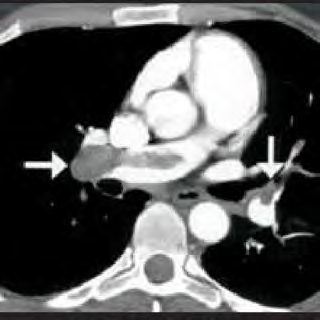

Certa idosa de 70 anos de idade é levada ao consultório médico por familiares, com relato de dor no peito há oito horas. Quanto a comorbidades, ela apresenta hipertensão arterial sistêmica e insuficiência cardíaca. Estava em casa assistindo à televisão quando sentiu uma dor súbita no peito, de moderada intensidade, que piora com a inspiração profunda, irradiando para o dorso, em queimação e associada a palpitações e a falta de ar importante, mesmo em repouso. Nega náuseas e sudorese. Não melhora após tomar dipirona. A dor continua da mesma forma, mas o que levou os familiares a procurarem atendimento foi a piora da falta de ar. Faz uso de losartana, atenolol, espironolactona, AAS e sinvastatina. Nega etilismo e informa que tinha o hábito de tabagismo, mas parou há mais de 10 anos. Tem histórico anterior de cirurgia de artroplastia de quadril há mais de um ano. Tem ficado muito tempo em repouso, assistindo à TV, principalmente depois da pandemia de Covid-19. Ao exame físico, constatam-se PA = 89 mmHg x 59 mmHg, FC = 125 bpm, FR = 27 ipm e SatO2 = 89% em ar ambiente. A paciente está afebril, em estado geral regular, lúcida, orientada e comunicativa. As auscultas pulmonar e cardíaca mostram-se sem alterações. Observam-se abdome inocente, membros inferiores com cacifo + discreto e simétrico, panturrilhas livres e pulsos preservados. A paciente realiza o eletrocardiograma e a tomografia de tórax, conforme representado nas imagens a seguir.

Disponível em: <https://www.researchgate.net/>.

Acesso em: 12 nov. 2020.

A tomografia apresenta uma área compatível com infarto miocárdico transmural, que é compatível com infarto agudo do miocárdio silencioso.